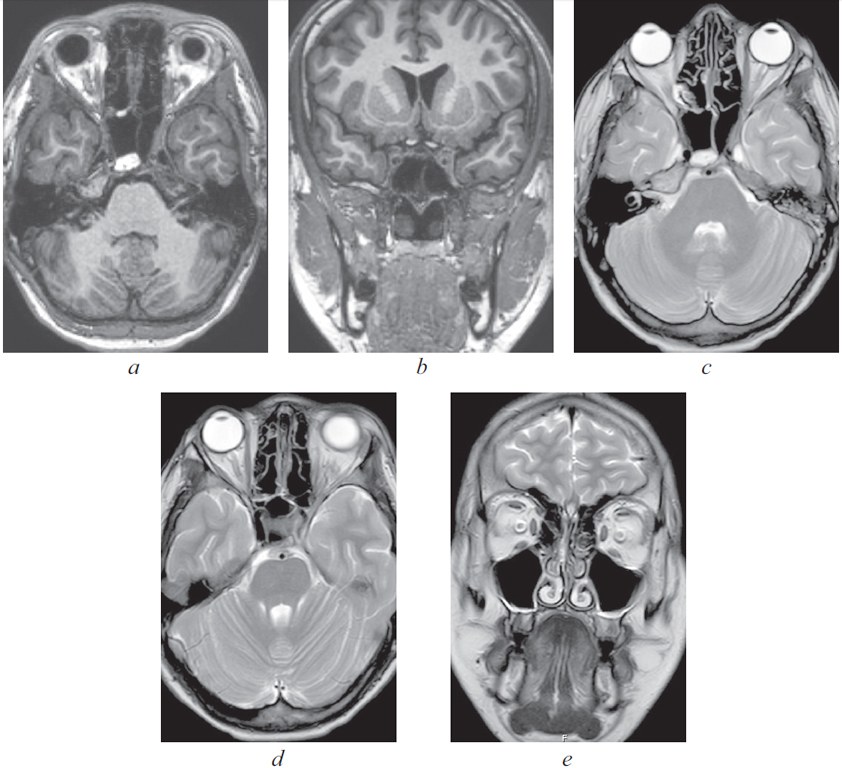

По результатам МРТ головного мозга от 16.06.2021 (рис. 2): МР-признаки подоболочечного скопления жидкости с высоким содержанием белка, воспалительных изменений оболочек в левой лобной области. Картина соответствует субдуральной эмпиеме.

Рис. 2. Магнитно-резонансная томография головного мозга от 16.06.2021: а — сагиттальная проекция в режиме Т2. Прослеживаются воспалительные изменения оболочек в левой лобной области. Картина соответствует субдуральной эмпиеме; b — аксиальная проекция в режиме Т2. Снижение пневматизации левой верхнечелюстной пазухи, пристеночный отек слизистой; c — аксиальная проекция в режиме Т2. Снижение пневматизации клеток решетчатого лабиринта; d — аксиальная проекция в режиме Т2. Воспалительные изменения оболочек в левой лобной области, субдуральная эмпиема

Fig. 2. Magnetic resonance imaging of the brain from 16.06.2021; a – sagittal projection in T2 mode. Inflammatory changes in the membranes in the left frontal region are traced. Picture consistent with subdural empyema; b – axial projection in T2 mode. Decreased pneumatization of the left maxillary sinus, parietal edema; c – axial projection in T2 mode. Decreased pneumatization of cells of the ethmoid labyrinth; d – axial projection in T2 mode. Inflammatory changes in the membranes in the left frontal region, subdural empyema